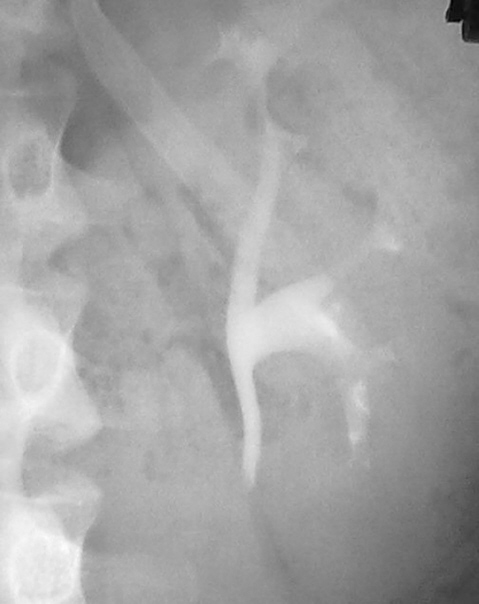

На мой взгляд, препятствие в мочеточнике есть, и складывается впечатление, что оно, хоть и мало, но обтекаемо.

Субстрат препятствия в левом мочеточнике, в данном конкретном случае, тоже за границами-пределами внутривенной урографии, может быть и камешек, может быть и сгусток, может быть всякое. Была надежда на УЗИ, но УЗИ надежд не оправдало…

Валентин Львович, я тоже "грешу" на кровяной сгусток.

Значит мысли сходятся...